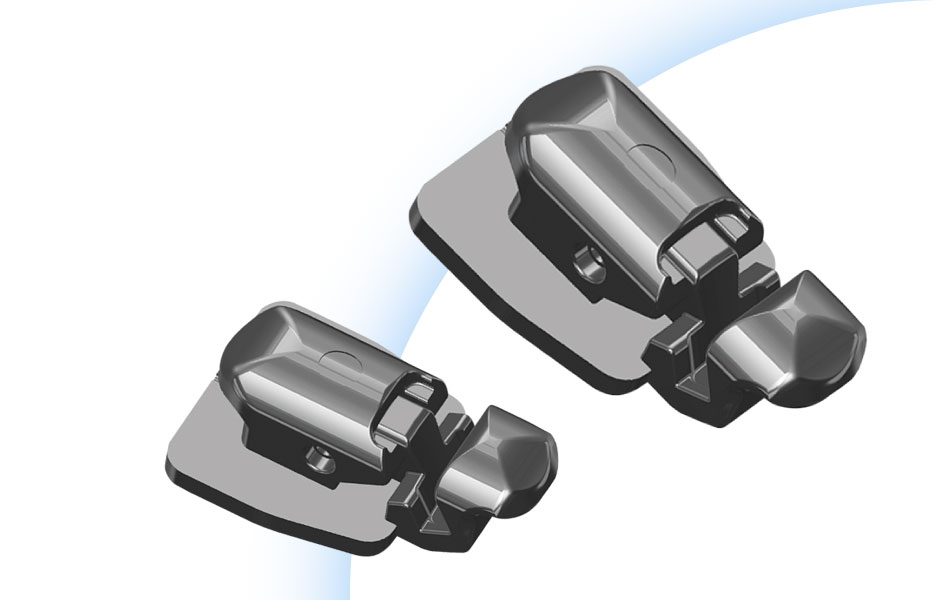

Лингвальные брекеты

Лингвальные брекеты крепятся на внутренней стороне зубов и не видны снаружи. Разработали их специально для тех, кто стесняется носить тяжелые неэстетичные конструкции или просто не хочет портить свой внешний вид установкой наружных моделей, меняющих эстетику в худшую сторону.

Ортодонтическое лечение проводится в более комфортной психологической обстановке, пациенты легко преодолевают психологические барьеры. Лингвальные модели брекет-систем называют внутренними в отличие от наружных, вестибулярных. Эти модели впервые появились около 50 лет назад, и до сегодняшних времен ведется разработка более совершенных вариантов.

В стоматологической клинике «Интердентос» в Королеве для каждого пациента устанавливается индивидуальная система лингвальных брекетов с уникальными соединительными элементами, изготовленная по сертифицированным технологиям.

Материалами изготовления являются прочные сплавы, с участием хрома, никеля, стали. Лечение зубов проводится на профессиональной основе, создавая стабильный результат на многие последующие десятилетия.

Типы по креплениям брекетов:

- Лигатурные, характерны крепления с обратной стороны металлической дуги к брекету замочками или резинками;

- Самолигирующие (безлигаурные)

Основные составляющие – металлическая дуга и эластичное кольцо, с регулировкой степени натяжения дуги по мере изменений расположения корней зубов. Самолигирующие брекет-системы отрегулированы изначально, поэтому приходить к стоматологу придется реже.

Мы используем в своей практике брекеты известных американских и немецких производителей, изготовленные по самым передовым технологиям.